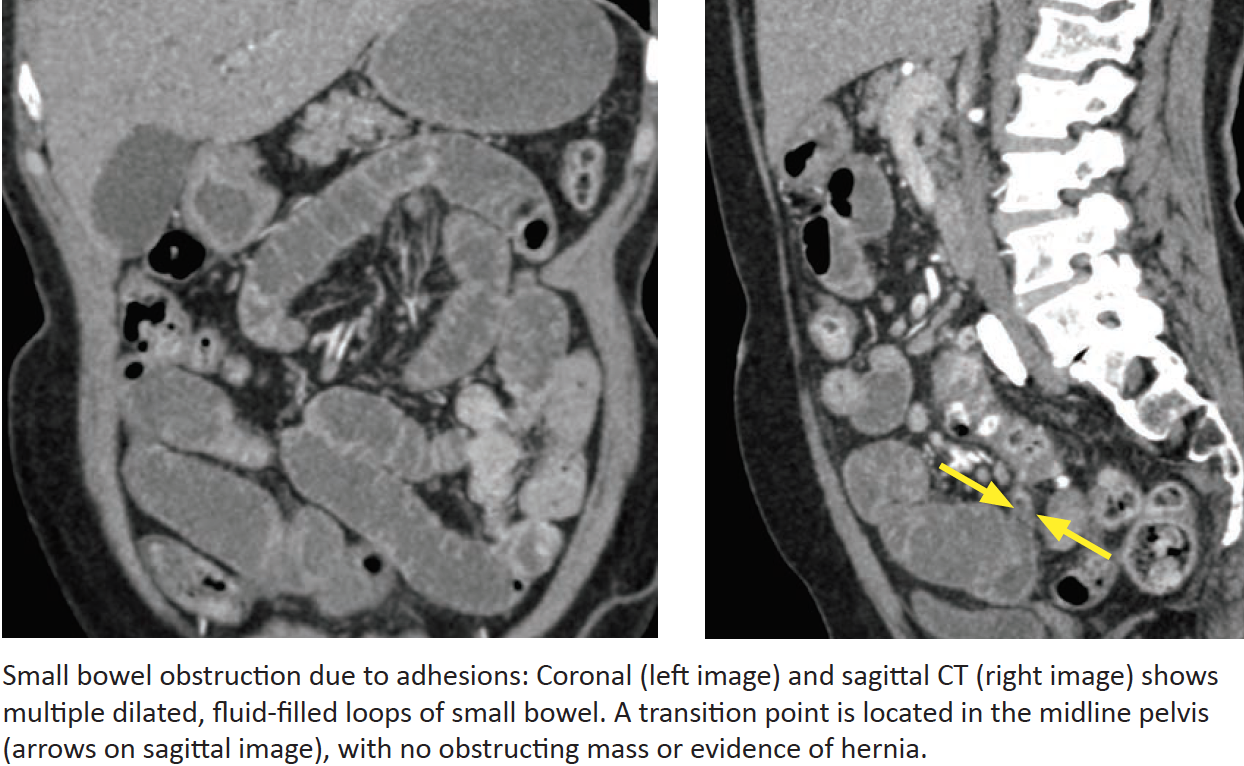

Obstruction due to Adhesions

Why do adhesions occur? What is the most common cause of SBO?

How do you diagnose adhesions on CT?

The vast majority of patients with SBO due to adhesions have had what in the past?